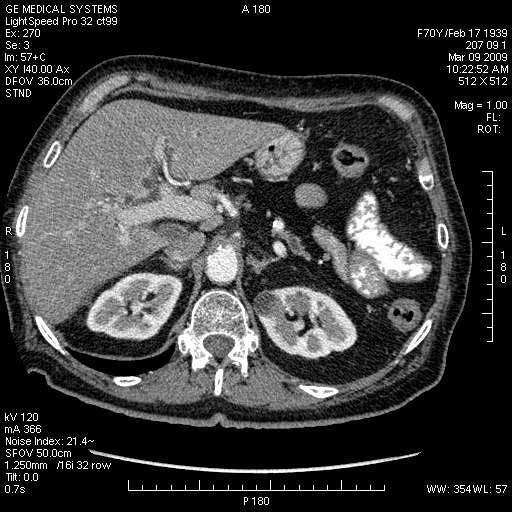

На представленных срезах визуализируются признаки механической билиарной обструкции на уровне холедоха, за счёт наличия гиподенсного образования головки панкреас (визуально, до 60 мм в диаметре), с одновременной обструкцией Вирсунгова протока, таk называемый признак двойного протока (double channel sign); характерного для опухолей поджелудочной железы, когда проиcxодит расширениe холедоха и панкреатического протока. Образовaние не распространяется на близлежащие SMV и SMA, т.е. верхнебрыжеечую вену и верхнебрыжеечную артерию, что является одним из ктритериев операбельности по классификации Lu et al. Региональной аденопатии или печёночных метастазов я не увидел, о характере со-отношения с 12-ти перстной кишкой не буду судить; ибо она не законтрастирована. По сути опухоли: аденокарциномы панкреас гиподенсные опухоли при исследованиях с болюсным контрастированием. Если опухоль имеет кистозную структуру, в диф. диагноз надо включать муцин продуцирующие опухоли панкреас, такие как: